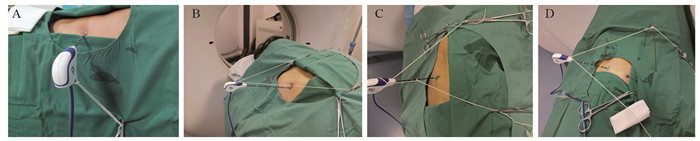

患者取多种体位,以其舒适、方便术者操作为目的。CT扫描参数:层厚1.25 mm,层间距1.25 mm。将定位栅放置在拟穿刺体表部位,平静呼吸状态下确定进针点、进针方向和深度。胸壁消毒、铺巾和麻醉后,经进针点、沿进针方向将消融针插入胸壁。取长100 cm白色细丝线一条,其中间固定在消融微波针针杆或尾部,两端甩出线头50 cm,根据肺CT显示针尖与结节的空间位置,牵拉两端丝线的方向和张力,调整针尖方向(调针),并用血管钳将丝线固定在铺巾表面,见图 1。

当针尖指向结节时,向前推送针体(进针),即调针、进针序贯进行(序贯穿刺模式)。随后,CT扫描核实结节与针尖位置,如果针尖方向偏离肺结节,则再次调整丝线的牵拉方向和张力,当针尖指向结节后,向前推送针体,直至针尖插入结节中心部位,启动消融过程,见图 2。本操作由两位有18年肺穿刺经验的医师独立完成。

本研究应用挂线方法包括:单线针尾挂线方法(图 1A):当针体呼吸摆动小或无时,适宜应用本挂线法调整针尖方向;双线(针尾、针杆)挂线方法(图 1B~C):(1)当针体呼吸摆动较大时,适宜应用双线挂线对抗针体摆动,特别丝线牵拉方向与针体摆动方向一致时;(2)当消融针尖插入胸壁或表浅时,体外针体受重力和呼吸作用发生偏移,引起针尖移位,适宜应用双线(甚至三线)对抗针体受重力和呼吸作用发生偏移,稳定针体和针尖方向;(3)当针体与CT扫描床平行或近乎平行方向进针时,针尾受重力作用下垂,适宜应用双线保持预设针体位置和方向(图 1B~D);支架辅助针尾挂线方法(图 1D):主要用于针体与CT扫描床平行或近乎平行进针时,或与胸膜切线平行路径进针时(图 2D~E),这时牵拉丝线与消融针成角过小,丝线牵拉力矩小,若要调整针尖方向需要加大拉力,丝线张力增加容易拖拽孔巾移位,甚至引起针尖非意愿性向前移动。单或双支架改变了力的作用点,增加了丝线牵拉力矩,血管钳丝线固定点受力明显减小。